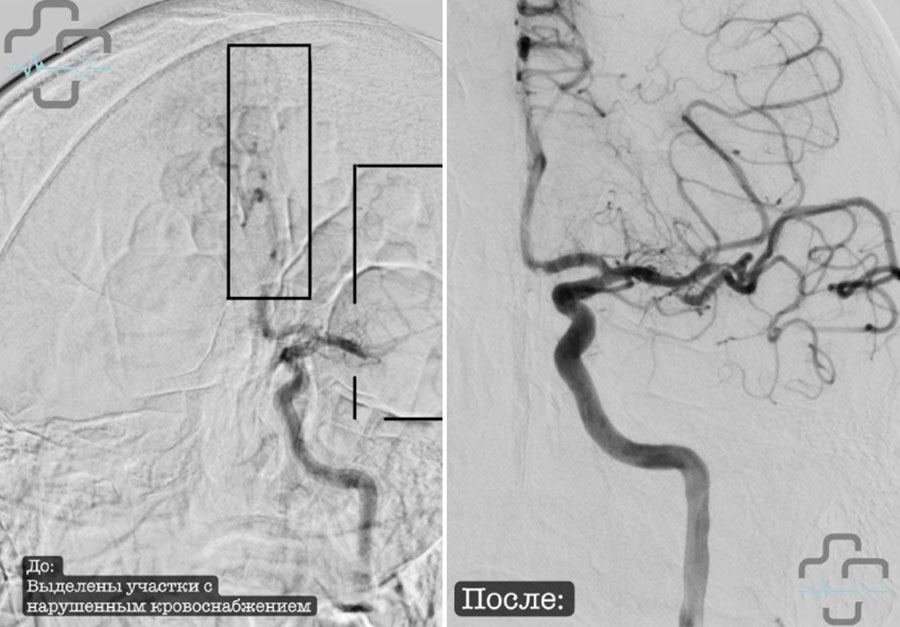

Хирурги регионального сосудистого центра Орской городской больницы спасли жизнь 16-летнему пациенту. Они извлекли тромб из левой средней мозговой артерии подростка.

Несовершеннолетнего пациента доставили в сосудистый центр с клиническими признаками острого нарушения мозгового кровообращения. После комплексного обследования подтвердилось, что произошел инсульт. Подростку в кратчайшие сроки провели операцию. Заведующий отделением рентген-хирургических методов диагностики и лечения Александр Григорьев успешно удалил тромб из левой средней мозговой артерии пациента.